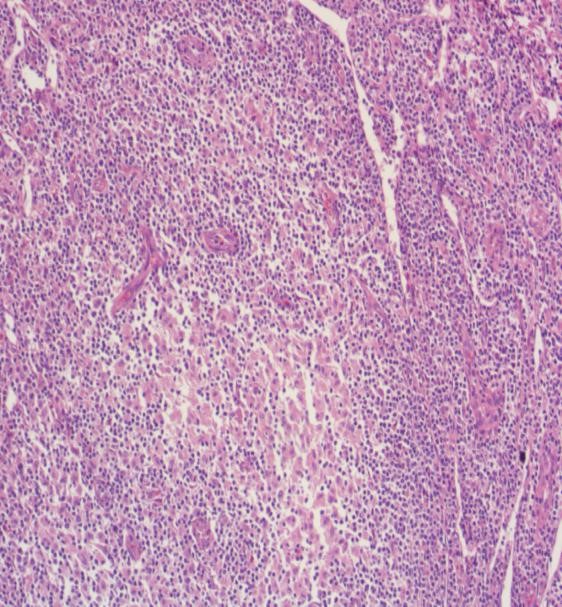

考虑患者常规检查已完善,予行PET-CT:1.双侧颈部、双侧锁骨区、双侧胸大肌间隙、双侧腋窝、纵隔内、双侧盆壁、双侧腹股沟多发大小不等淋巴结,FDG代谢轻度增高,SUV最大值约2.85,炎性可能,建议腹股沟淋巴结活检除外淋巴瘤可能。2.脾脏肿大,未见放射性摄取异常增高(见图2)。

图2